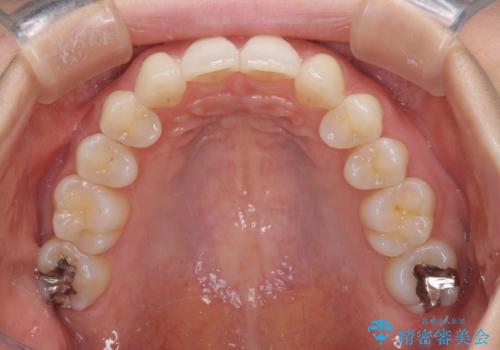

上顎前歯が2本欠損 インビザラインによる叢生の解消

- 深い咬み合わせと前歯のデコボコを気にして来院された患者様です。

上顎前歯2本が欠損しているため、妥協的なゴールを設定しインビザラインで矯正治療を行うこととしました。

上下前歯の大きさのアンバランスにより、深い咬み合わせと奥歯の咬みにくさがなかなか解決されず、治療に長期間を要することとなりました。